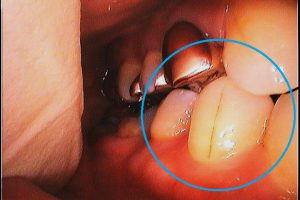

↑このように歯に亀裂の入っている方や、